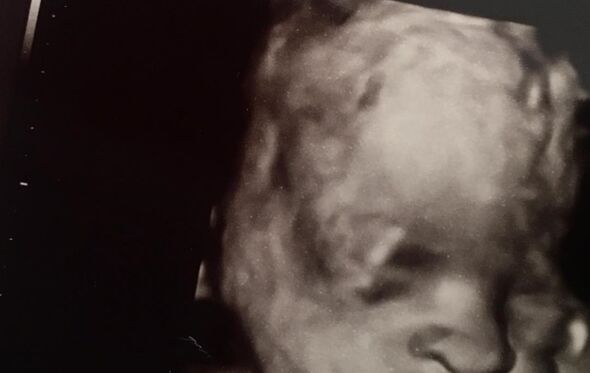

Quem acompanha a conta de Instagram do rapper Skepta, atual companheiro de Naomi Campbell, não queria acreditar no que estava a ver. O músico partilhou uma imagem de uma ecografia com o nome de Baby Adenuga, o seu próprio apelido pois o seu verdadeiro nome é Joseph Junior Adenuga.